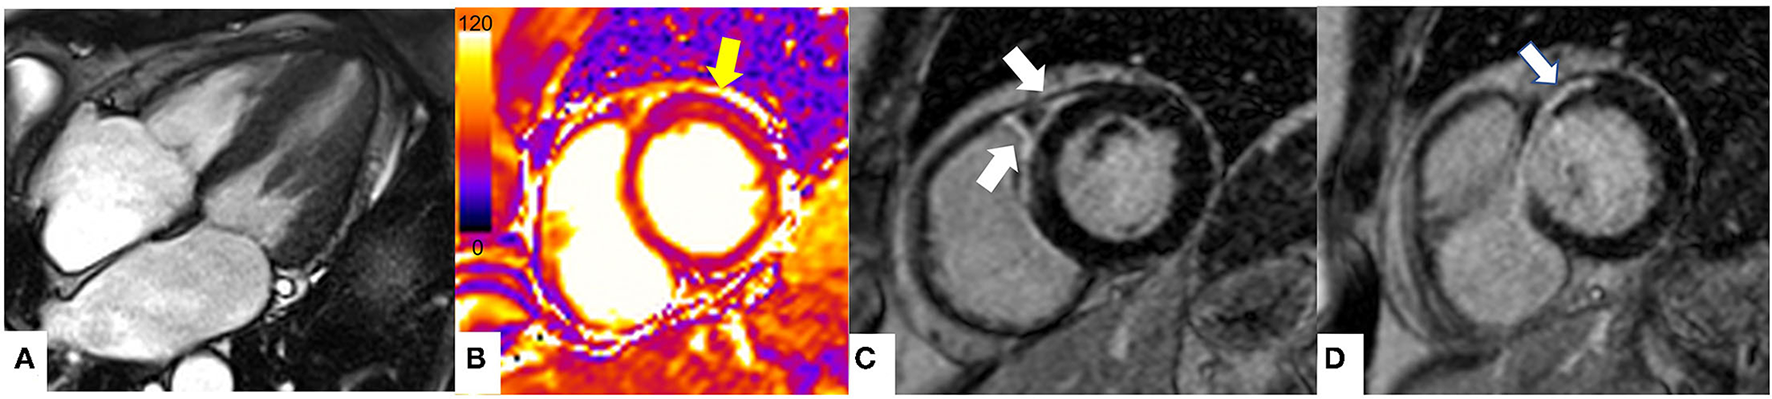

Figure 5 shows the CMR findings of systemic diseases with cardiac involvement presenting with possible MINOCA.

Figure 5

The role of CMR in non-ischemic cardiomyopathies mimicking MINOCA. CMR findings in a patient with known cardiac sarcoidosis presenting with chest pain. (A) Steady state free precession sequence (SSFP) cine sequence 4 chamber (end-systole) showing preserved ventricular systolic function (B) T2 mapping (basal segments) showing high T2 values (arrow) in the basal anterior wall (T2 = 62 ms, normal values T2 < 55 ms at 1.5 T) suggestive of myocardial oedema. (C, D) Late gadolinium enhancement imaging (LGE) at the level of basal segments demonstrating prominent subepicardial to mid wall enhancement in the basal anteroseptum and anterior wall extending into the adjacent right ventricular anterior wall (arrows). The pattern of myocardial injury noted is in keeping with acute cardiac involvement in sarcoidosis.